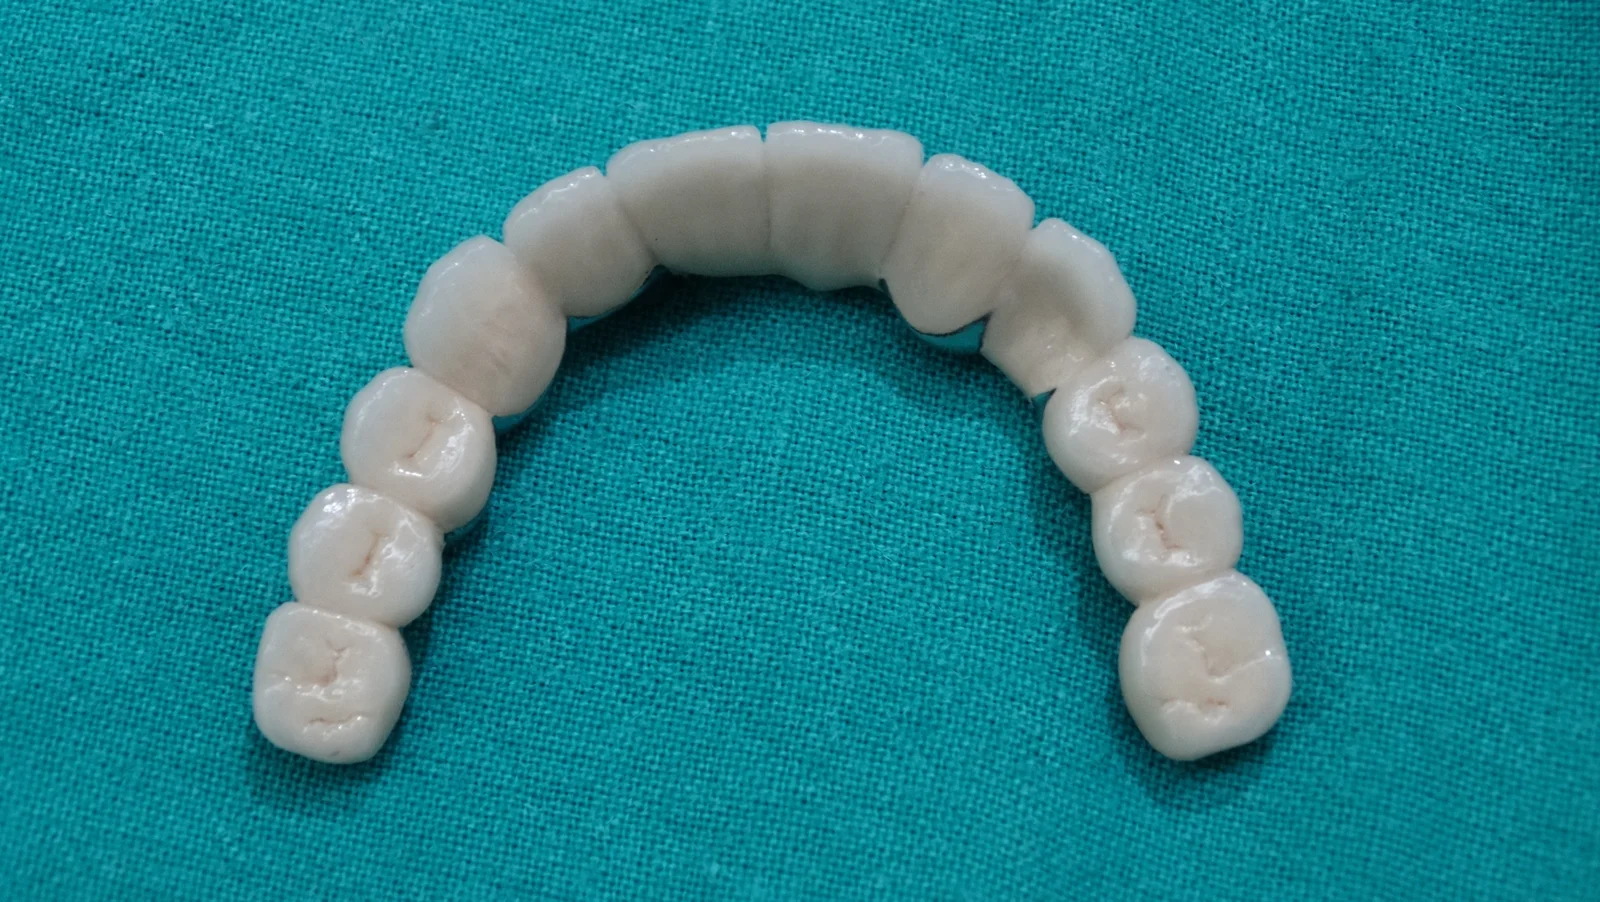

Implant Supported Fixed Teeth

Replacing all missing teeth with a permanent, fixed prosthesis that mimics the look, feel, and function of natural teeth. Explore our clinical transformations below.

Full Mouth Rehabilitation

Clinical Case Progression